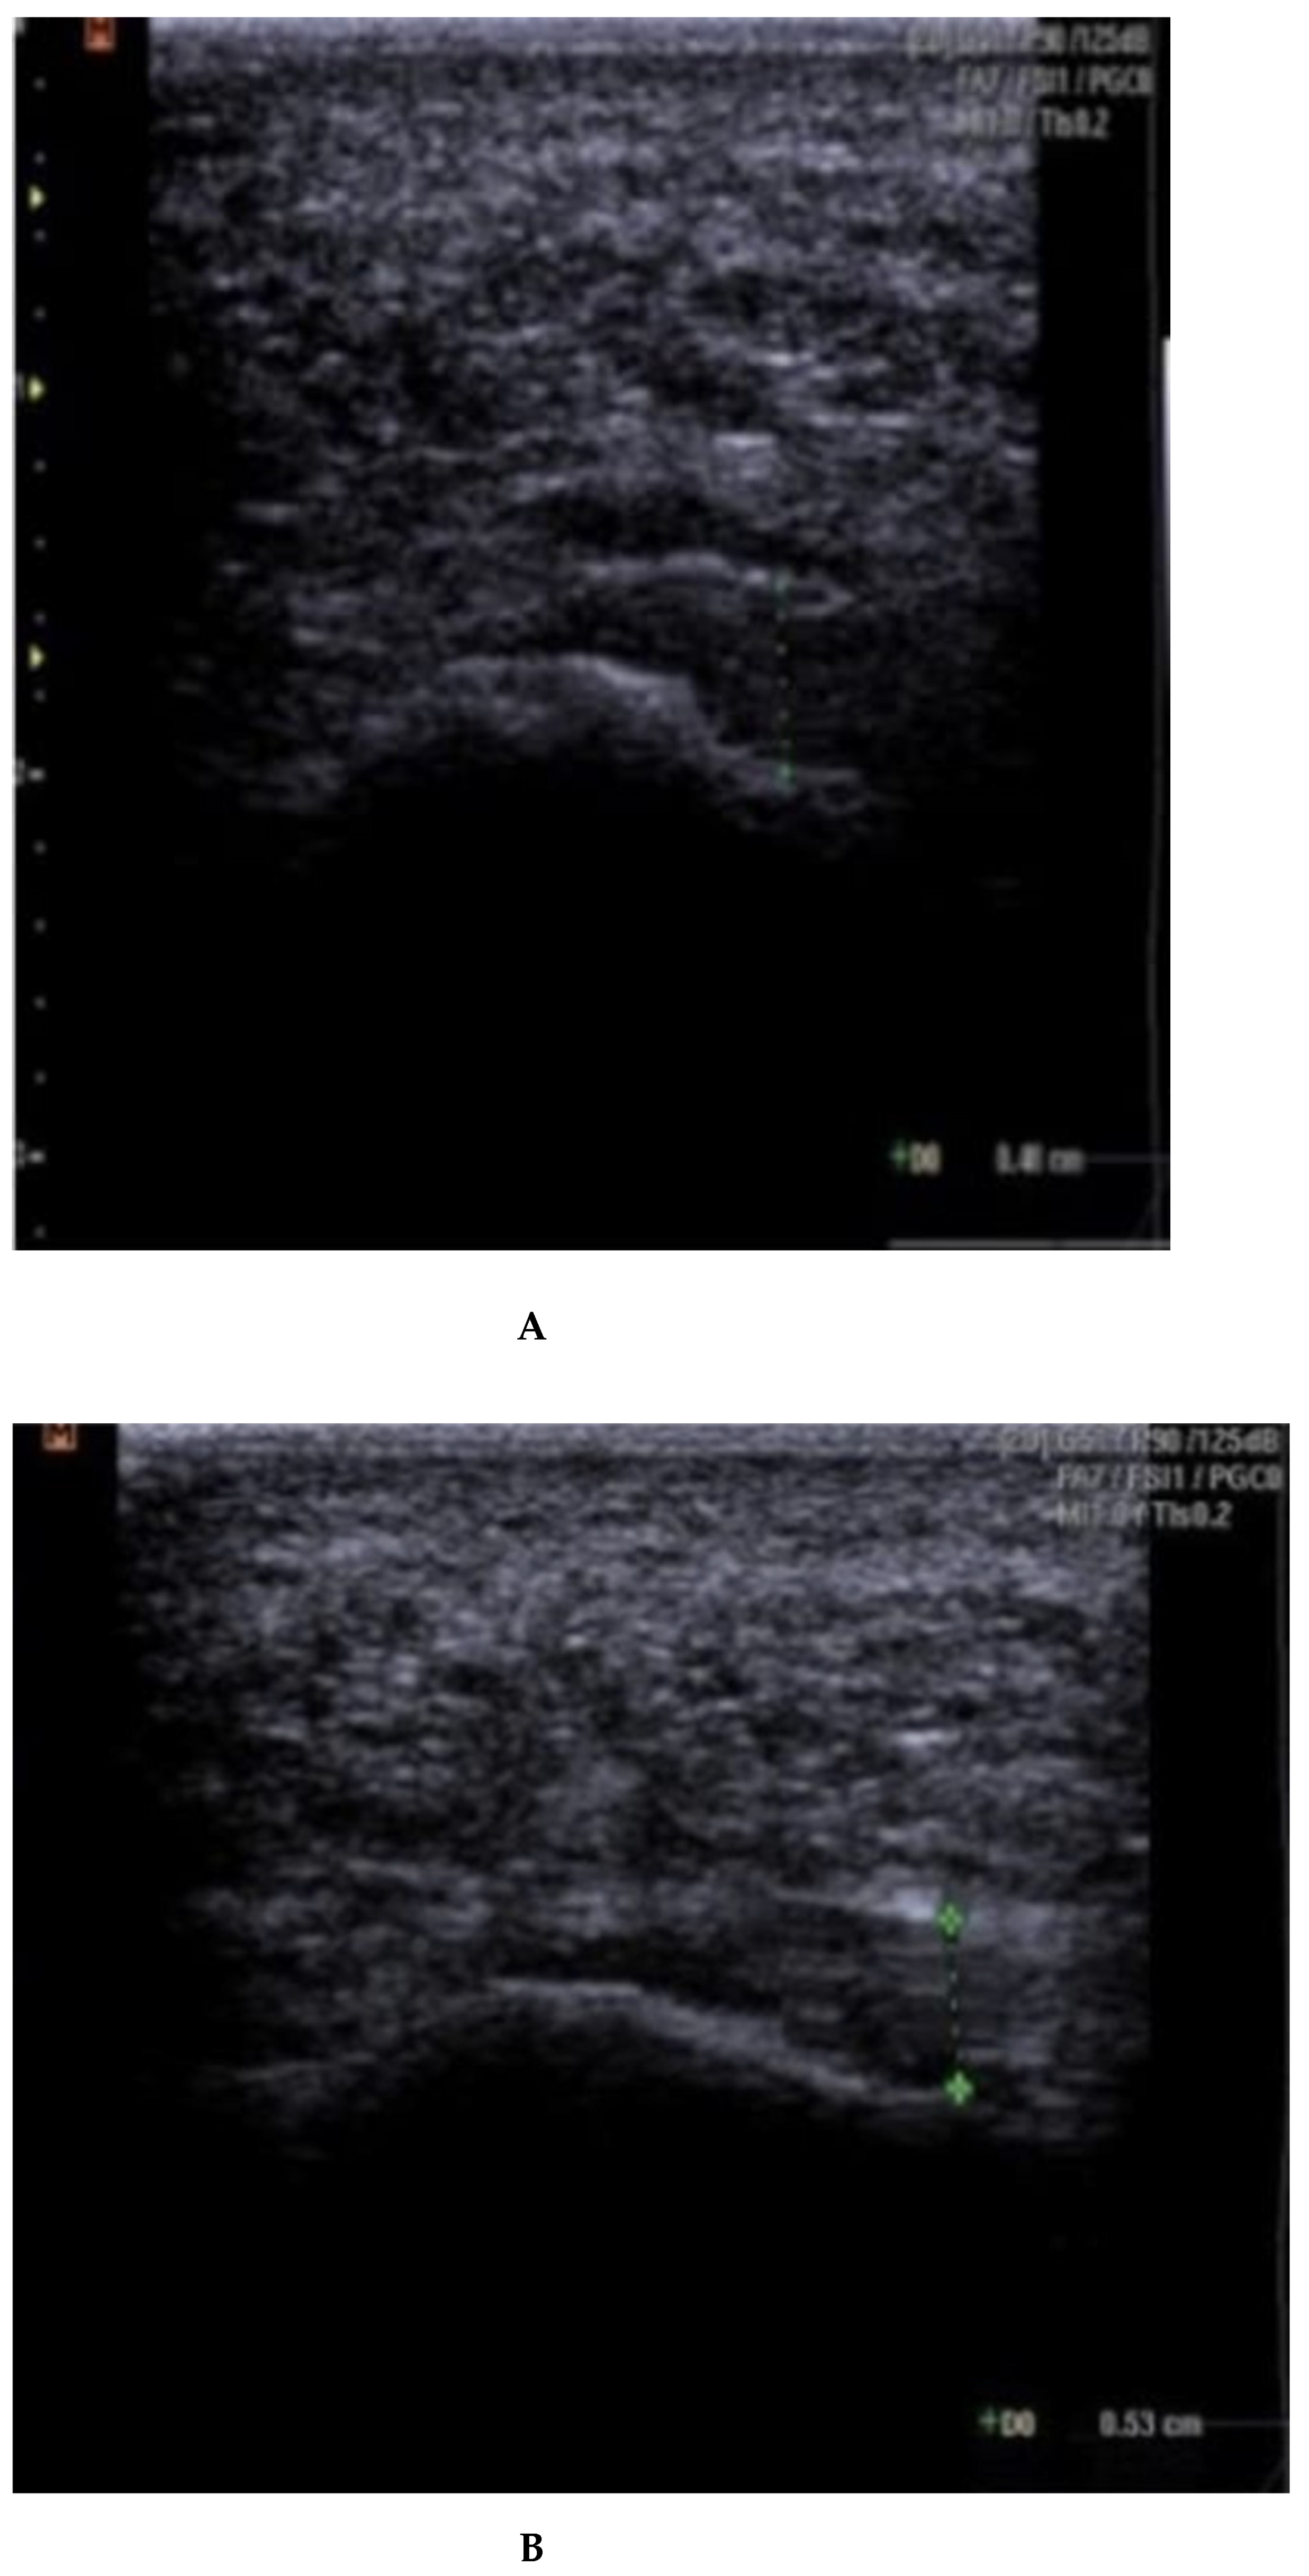

Fascia thickness and echogenicity. All patients had an increased plantar fascia thickness (3.50–8.0 mm) at baseline when measured with MSKUS, and all had hypo-echogenicity. There was a significant difference in the reduction of the plantar fascia thickness between the two groups at 4 weeks follow-up in favor of CSI + TUS (p = 0.004, Table 5), as also shown in Figure A1 and demonstrated in ultrasound images in Figure A2 and Figure A3. At the 12-week follow-up, plantar fascia thickness was significantly higher in the CSI + TUS group (p = 0.012), with an insignificant difference in the decrease between both groups (p = 0.216).

Echogenicity change (Figure A2 and Figure A3) from hypoechoic to iso- or hyperechoic was statistically significant in both groups at 12-week follow-up, but no significant difference was found between the groups (p = 0.208; Table A1).

(A–C): plantar fascia thickness and echogenicity before, after 4 weeks, and 12 weeks follow-up (CSI followed by therapeutic US). (A). Plantar fascia thickness (0.55 cm) and echogenicity (hypoechoic) before CSI injection followed by therapeutic US; Ankles in 90° dorsiflexion; Images obtained just medial to the midline, at the proximal end of the plantar fascia, distal to its origin, from the medial tubercle of the calcaneus; Thickness of the plantar fascia was measured from the base of the medial calcaneal tubercle, where a bright echogenic line was easily visible. (B). Plantar fascia thickness (0.44 cm) and echogenicity (hypoechoic) after 4 weeks. (C). Plantar fascia thickness (0.41 cm) and echogenicity (hypoechoic) after 12 weeks.